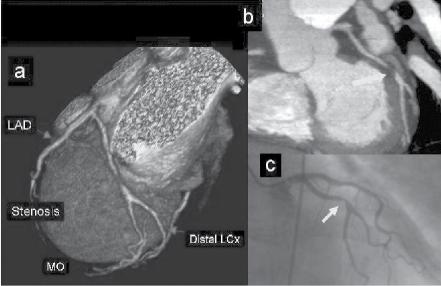

Figure 1.1 (A) Normal case: coronary angiography (left) and three‐dimensional CTA (right) showing normal left anterior descending (LAD, arrow) and left circumflex (LCX) coronary arteries. The latter is partially covered by the left appendix in CTA. (B) Normal case: coronary angiography (left) and CTA (right) showing a normal dominant right coronary artery (RCA). (C) An 85‐year‐old man with atypical chest pain: (a) Maximal intensity projection (MIP) of CTA with tight mid‐LAD stenosis that correlates perfectly with coronary angiography (b). (D) Similar case as (C) but with the stenosis in the proximal RCA. (a–d) CTA and (e) coronary angiography. (E) A patient with tight stenosis in the LCX before a bifurcation. (a) and (b) CTA and (c) coronary angiography. (F) These images show that CTA may also demonstrate the presence of stenosis in distal vessel branches, in this case in the posterior descending branch of the RCA. (a–b) CTA and (c) coronary angiography. (G) These images show that CTA (a, b) may delineate the length of a total occlusion and visualize the distal branches (see arrows in (b)). Collateral flow from the LAD to the RCA may be better visualized with CTA than with conventional coronary angiography (c: here only the RCA is shown). (H) A 42‐year‐old patient with a stent implanted in the LAD six months before. The patient complained of atypical chest pain and underwent CTA. The MIP images of CTA (a–c) show no significant restenosis, but some plaque formation in the left main trunk (d, circle) that was not well seen in coronary angiography (e). The degree of luminal obstruction by the plaque can be exactly measured by intravascular ultrasound (IVUS) (f). The ECG showed mildly inverted T waves in V1–V3 during follow‐up (see Plate 1 in color plates).

intervention (PCI) (Figure 1.1). CTA may provide additional diagnostic information for clinical decision‐making in contemporary stable chest pain patients with intermediate pre‐test probability for IHD (Hoffmann et al. 2017). In additional to narrowing, CTA can provide information on coronary distribution, including abnormalities in the origin and course of the arteries, and presence of coronary aneurysms. However, the accuracy of assessing the severity of coronary stenosis in highly calcified lesions and within stents is reduced.